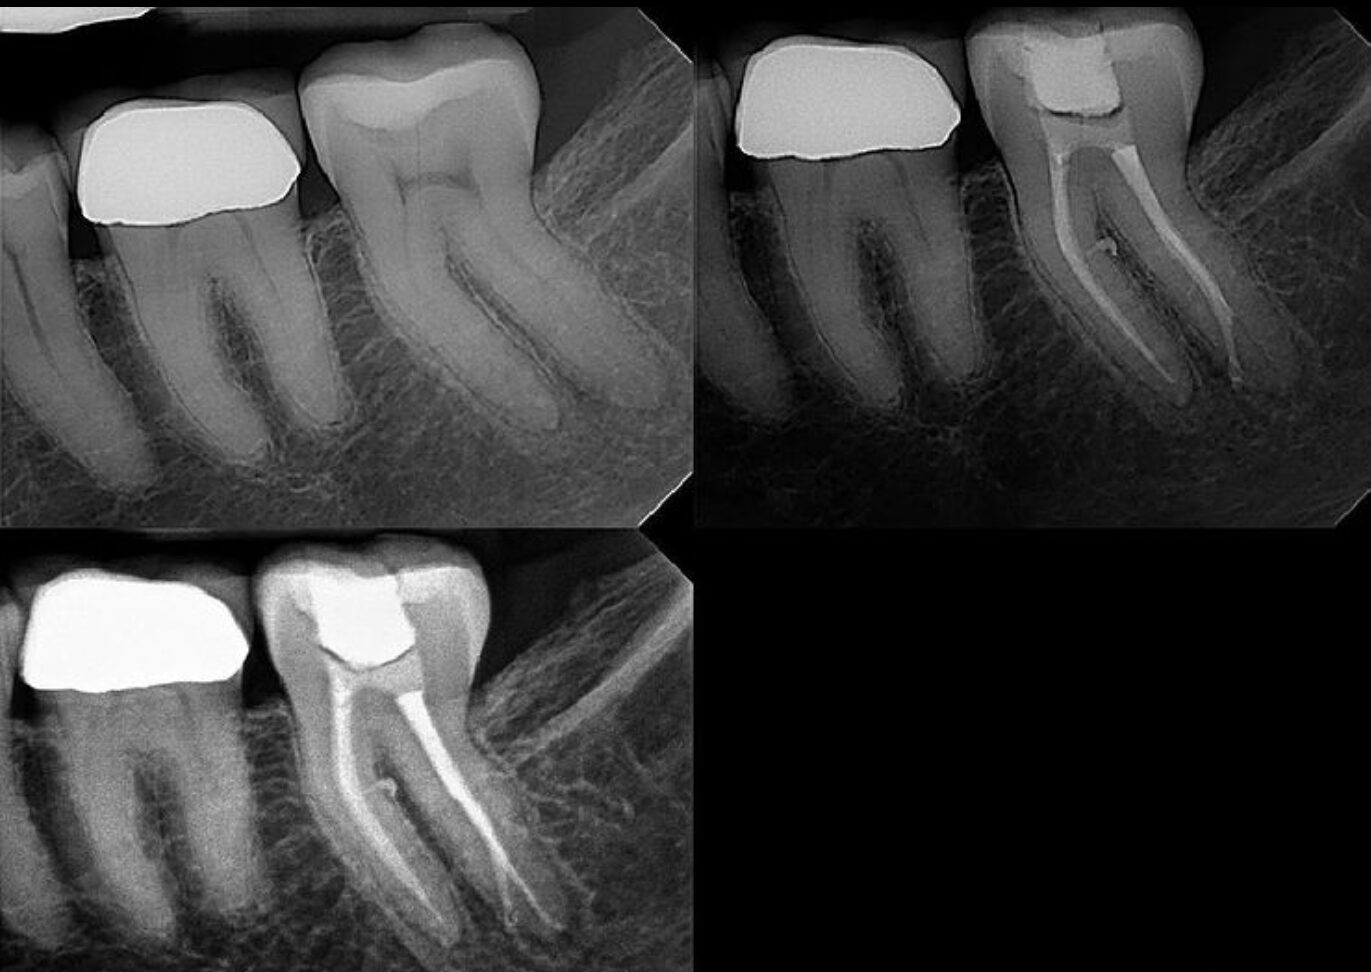

Case Studies

Discover all our case studies on Instagram by following @dana_point_endodontics and exploring our highlights or posts for in-depth insights and success stories!